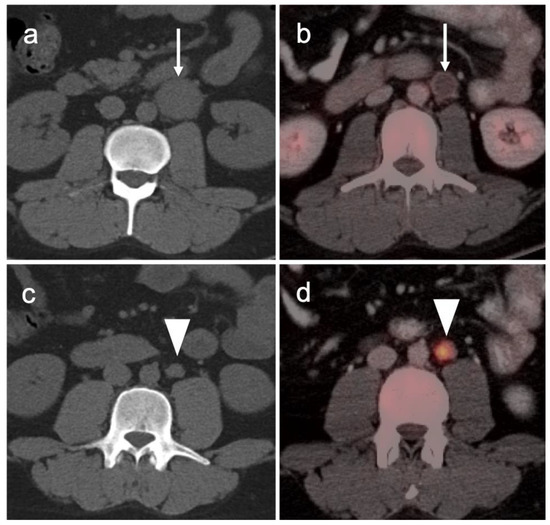

3.1. Prostate Cancer